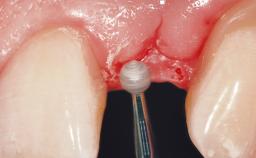

Immediate Flapless Placement of an Implant in a Maxillary Left Central Incisor Site

A 42-year-old female patient was referred to our clinic at the School of Dentistry of the University of São Paulo in November 2004, presenting a deficient restoration in the upper left central incisor. The clinical examination revealed no gingival retraction or any signs of gingival inflammation and, therefore, previous periodontal treatment was not considered. The patient presented a high lip line at full smile and a thin tissue biotype. This combination characterized a high-risk situation from an anatomic point of view, which required careful preoperative planning and cautious surgical execution.

Soft Tissue Anatomy Intact Defective

Soft Tissue Contour and Volume Ideal